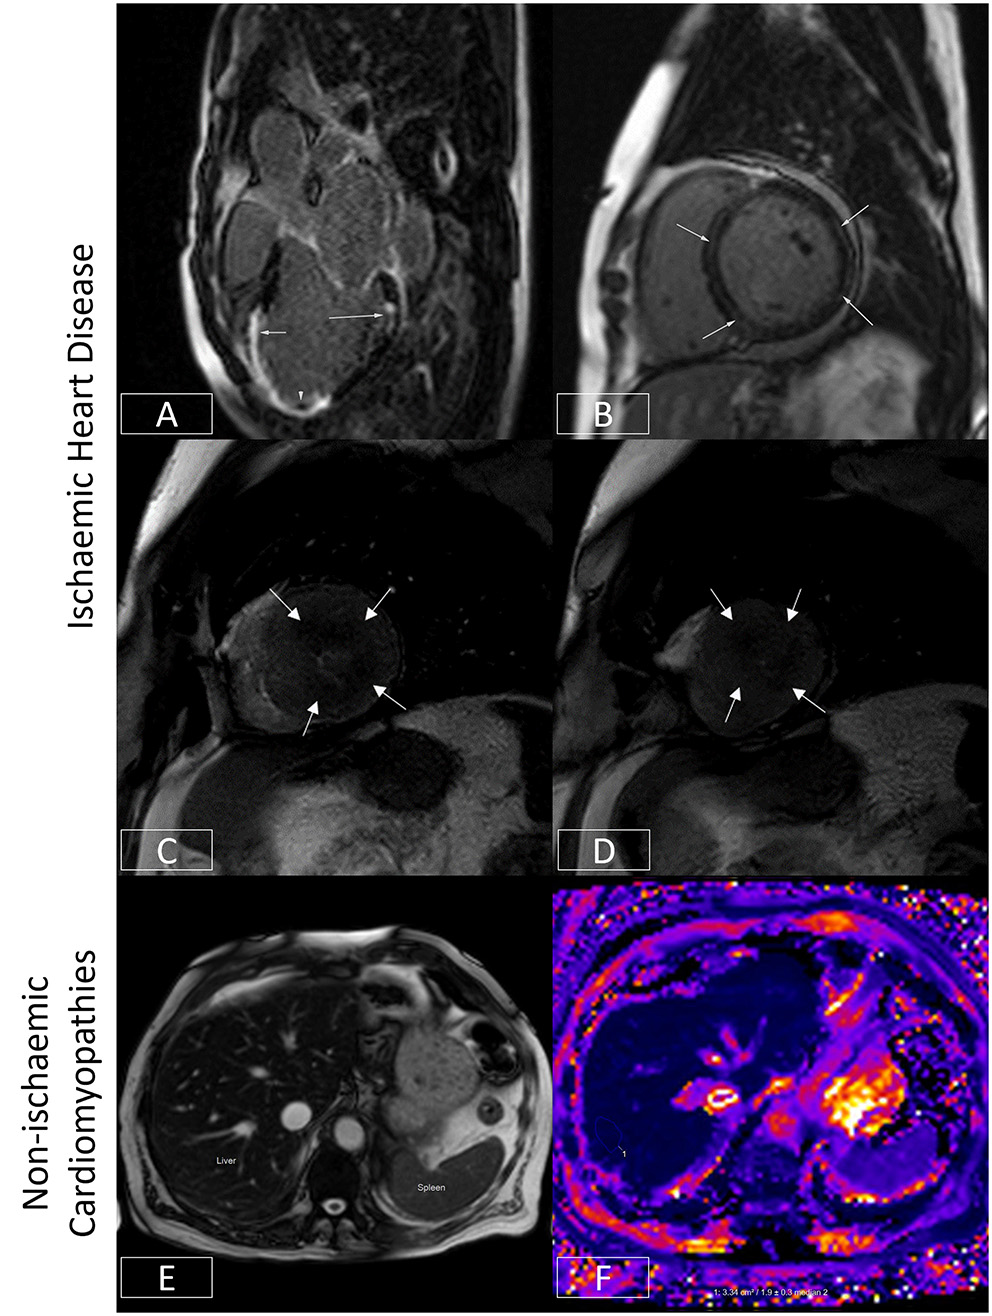

Figure 4

Ischaemic and non-ischaemic heart disease. (A) Late gadolinium enhancement sequence in the 3-chamber view. There is near transmural sub-endocardial enhancement of the mid-apical septum and apex (short arrow, mid-left anterior descending coronary artery territory). A signal void focus is also seen adherent to the apex (arrowhead). This represents a left ventricular thrombus. In addition, there is focal partial thickness sub-endocardial enhancement of basal inferolateral wall (long arrow, circumflex coronary artery territory), which spares the sub-epicardium (denoting an ischaemic etiology). The presence of infarcts in two different coronary territories alludes to the potential presence of multivessel coronary disease. (B) Late gadolinium enhancement sequence demonstrating a ring or circumferential pattern of non-ischaemic enhancement. The areas of enhancement involve the mid-wall or sub-epicardium, sparing the sub-endocardium. (C,D) Stress perfusion scan from a patient with hypertrophic cardiomyopathy. There is widespread circumferential sub-endocardial delayed arrival of contrast (hypoperfusion) at mid-ventricular level (C) and apex (D), typical of microvascular dysfunction. (E,F) Bright blood axis scout at upper abdominal level (E). The normal liver should have signal characteristics similar to the spleen (marked). However, in this patient with hepatic iron overload, the spleen appears almost black due to accelerated dephasing of spins brought about by the increasing field inhomogeneity generated by intrahepatic iron stores. This effect can be used to quantify liver iron levels (F). Here, the liver is ~1.9 ms, denoting moderate hepatic iron overload (normal > 6.3ms) equivalent to ~5–10mg iron/g dry weight.

In patients with ischemic heart disease, the distribution of LGE can localize infarcts to specific coronary territories (Figure 4A), and the transmural extent can determine the likelihood of underlying myocardial viability (75). By imaging the first pass of contrast through the myocardium under conditions of vasodilator stress (typically achieved with adenosine or regadenoson), myocardial perfusion abnormalities may be identified which may signify myocardial ischemia (76). When the epicardial coronary arteries are unobstructed, contrast arrives synchronously and homogeneously in all supplied myocardial segments. However, where there is a hemodynamically significant stenosis in a given coronary artery, that vessel will already be maximally vasodilated at baseline. The administration of a vasodilator will thereby augment blood flow (and so the arrival of contrast) to unobstructed coronary arteries, allowing areas of hypoperfusion to be delineated by the delayed and reduced arrival of contrast to the already maximally dilated stenosed vessel (76). This technique can therefore be used to diagnose the presence of coronary disease (77) or where this is already known, determine the functional significance of a given stenosis identified using an anatomical imaging technique such as invasive coronary angiography or CT coronary angiography. As mentioned previously, this technique is frequently used in tandem with LGE imaging to assess for myocardial ischemia and viability and thereby determine the need for or to guide revascularization (76). Recent US chest pain guidelines now regard this as a class I indication for stress CMR (level of evidence B) (69). Advances in sequence design, image processing, and quantification techniques now enable myocardial blood flow to be measured at the voxel level with high in-plane spatial resolution (78–83). The latter allows microvascular dysfunction to be elucidated non-invasively (79, 84, 85) (Figures 4C,D), and for ischemic burden to be accurately calculated (81, 86). Quantification techniques also appear to improve the ability to correctly identify multivessel coronary disease (87).

Non-ischemic Cardiomyopathies

The ability to quantify tissue characteristics has enabled various MR relaxation parameters to be used as biomarkers for diagnosis and to guide therapy (42, 88). The seminal example of this is the development of imaging (Figures 4E,F), which has enabled non-invasive hepatic and myocardial iron quantification (49). By allowing the early diagnosis of iron overload cardiomyopathy and timely initiation and titration of chelation therapy, this has been credited with significantly reducing the risk of death from heart failure in patients with thalassemia (89). The development of T1 mapping techniques (see Section Quantitative CMR Techniques) has found applications in detecting interstitial fibrosis, and by measuring post-contrast T1 together with the knowledge of the patient's hematocrit, the estimation of extracellular volume fraction (ECV) has made it possible to track pathologies such as cardiac amyloidosis (42). This is of growing relevance as these conditions are increasingly amenable to novel therapeutics which can stabilize or even potentially partially reverse cardiac amyloid deposition (90). Thus, CMR is regarded as a class I indication for the evaluation of infiltrative disease and suspected iron overload (level of evidence C) (63).